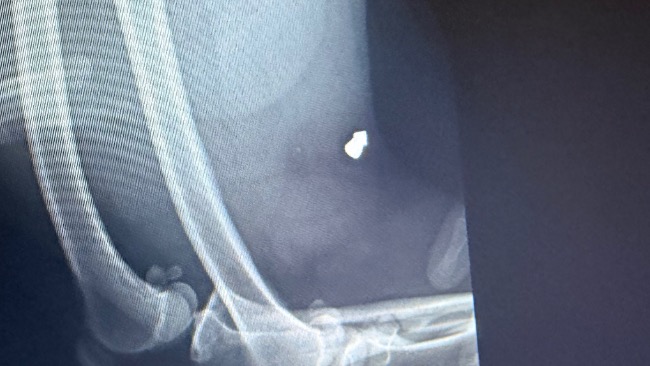

RTG, echo serca, USG jamy brzusznej — nie możemy pozwolić sobie na kompromisy w diagnostyce. Prosimy o pomoc. Kazimierz nie może czekać.